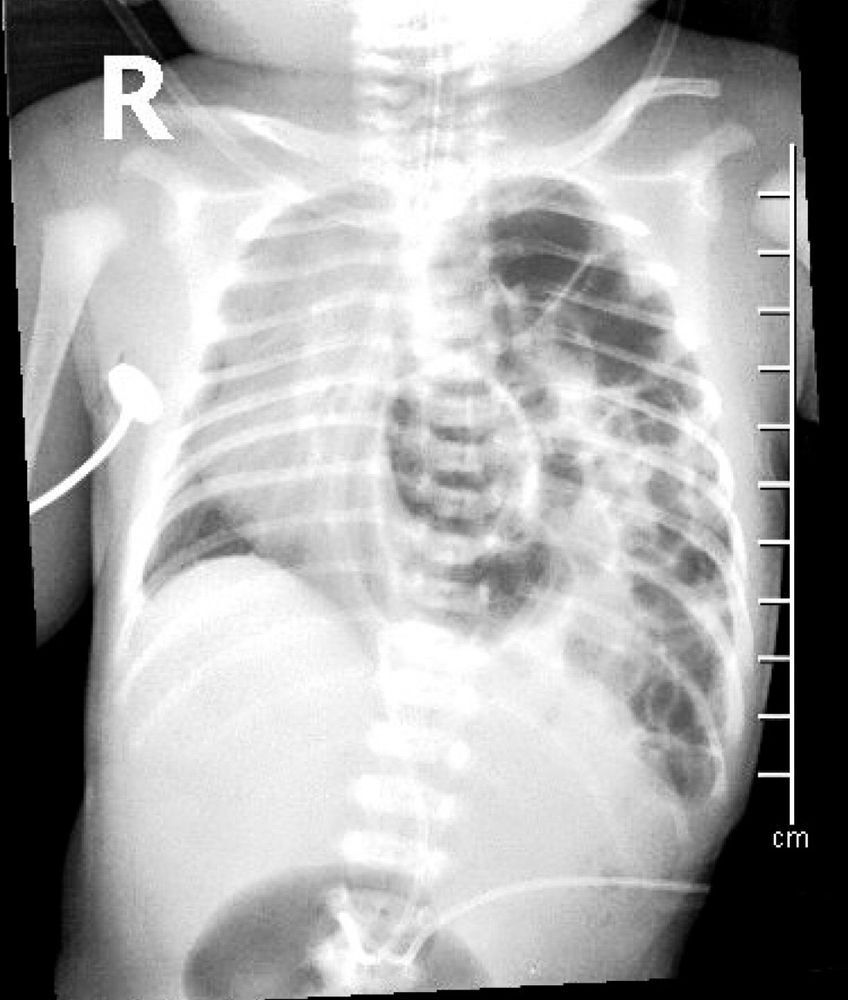

Rentgenový snímek novorozence s vrozenou brániční kýlou, Zdroj: Shutterstock

Některé děti se s brániční kýlou již narodí – odhaduje se, že tím trpí jedno z 2500-5000 narozených dětí. Může se projevit a odhalit už u novorozenců hned po porodu, ale klidně i po několika měsících. V některých případech se jí dokonce podaří odhalit prenatálně už u plodu. Pokud je kýla na životě ohrožující, přistupuje se k operaci.